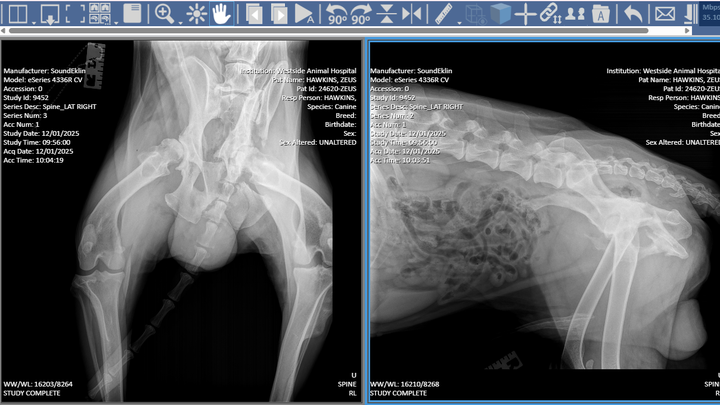

Because Zeus did not receive immediate medical care, his injuries worsened over time. He suffered a broken pelvis, which led to severe muscle atrophy in his left leg, leaving him in significant pain and unable to properly use it. Despite everything he has endured, Zeus continues to fight with incredible strength and resilience.

At this time, Zeus is being medically managed and closely monitored while awaiting an orthopedic surgical evaluation to determine the best course of treatment. He is currently prescribed Gabapentin, Carprofen, and Trazodone to help control pain, inflammation, and to keep him safely sedated in order to prevent further injury or additional damage while we await definitive surgical care.

There is a possibility that Zeus may need to undergo left leg amputation in order to relieve pain and give him the best chance at a comfortable, mobile life. The minimum cost of care is estimated at $8,000, and it may increase depending on the surgical treatment required, post-operative care, rehabilitation, and follow-up visits.